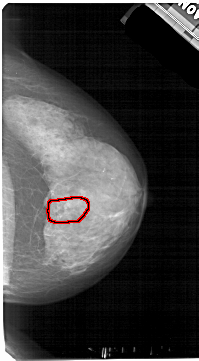

A_1605_1.RIGHT_MLO

RIGHT_MLO LINES 5491 PIXELS_PER_LINE 3091 BITS_PER_PIXEL 12 RESOLUTION 43.5 OVERLAY

FILE: A_1605_1.RIGHT_MLO.OVERLAY

TOTAL_ABNORMALITIES 1

ABNORMALITY 1

LESION_TYPE CALCIFICATION TYPE PLEOMORPHIC DISTRIBUTION SEGMENTAL

ASSESSMENT 4

SUBTLETY 3

PATHOLOGY BENIGN

TOTAL_OUTLINES 1

BOUNDARY